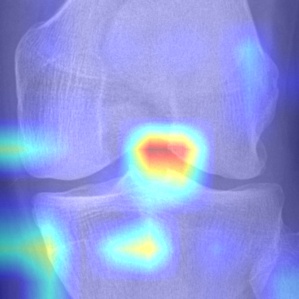

(f) our model

Figure 4: Localizations on knee joint images of KL-2 presented by Grad-CAM based on each series of models which archived the best performance. The original image with KL-2 is (a), the attention maps produced from the last CNN layer of corresponding models are (b),(c) and (d), and (e) represents the attention map produced by our model.

Finally, we presented attention maps to visualise the regions where models focus on. From the presented Grad-CAM images, all models selected can react to regions that cover the relevant characteristic of KL-2 to a certain extent. But at the same time, they also reacted to background noise, which may affect their performance of classification for invisible data. [On the contrary, thanks to the extraction of ROI, the siamese model can avoid this well…]

Firstly, the symmetry of the knee joint enables the Siamese network to learn the characteristic of both sides of the knee which determine the OA using less parameters. The obtained attention maps show that the most discriminative characteristic are located on both sides of the knee joint, which conforms to the description of KL-2 in the Kellgren and Lawrence system. We also proved that it makes sense to use multiple GAP layers to combine features from low to high level.